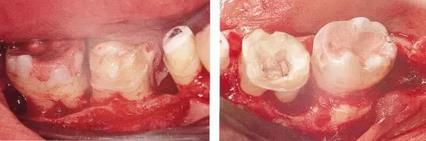

360截圖20170422102030273.jpg

▲圖11-3,4

▲圖11-3,4 齦瓣剝離翻開的狀態(tài)。右下6的遠(yuǎn)中牙根有較深的骨組織缺失,右下7的頰側(cè)有II度根分叉病變和近遠(yuǎn)中側(cè)有垂直型骨組織缺失。